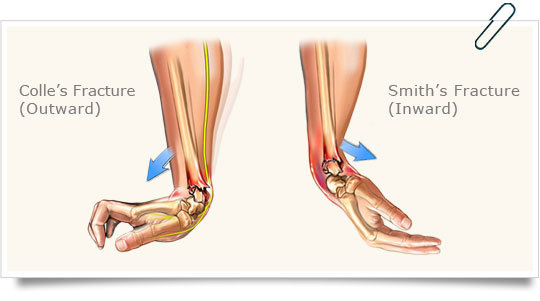

Most likely mechanism of injury?

Fall on outstretched hand

Shows distal radius fracture with shortening and dorsal displacment.

This injury is known as Colles’ fracture.

A fall with wrist in flexion may lead to?

Hyperflexion in addition to a ventrally displaced radius fracture (Smiths Fracture).